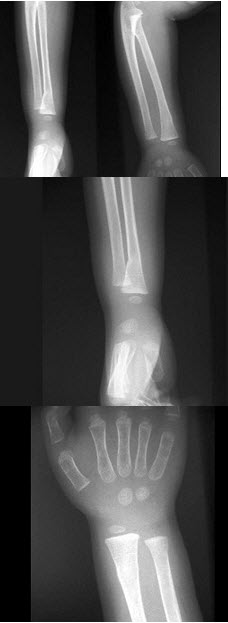

12、单项选择题

出生6个月的男婴,摔地后右手红肿,结合CR片,正确的骨折类型是()

A.青枝骨折

B.横行骨折

C.斜行骨折

D.粉碎性骨折

E.压缩骨折